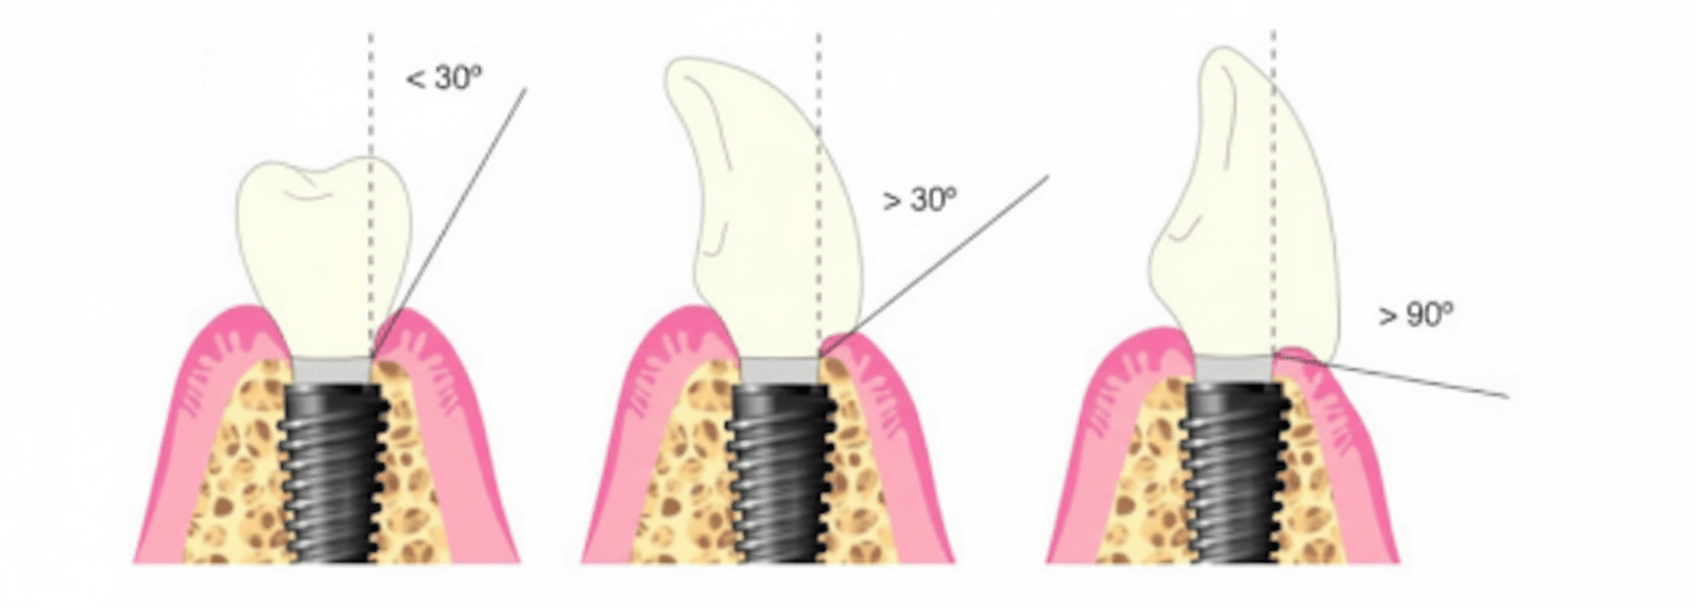

Der Gingivazenit bezeichnet den apikalsten (wurzelzugewandten) Punkt des Zahnfleischrandes, wenn der Zahn von der vestibulären (wangenseitigen) Seite betrachtet wird. Bei den oberen mittleren Schneidezähnen liegt dieser Punkt üblicherweise etwas distal (weiter von der vertikalen Mittellinie des Zahnes entfernt). Diese subtile Asymmetrie trägt zu einem natürlicheren und harmonischeren Verlauf des Zahnfleischrandes bei. Im natürlichen Gebiss bestimmt die Lage des Zenits die Kontur und Struktur des Zahnfleisches. Bei Implantatversorgungen stellt die Reproduktion oder der Erhalt dieses Punktes eine chirurgische und prothetische Herausforderung dar.

In der Implantattherapie, insbesondere im ästhetischen Bereich, wird der Gingivazenit bestimmt durch:

Wichtige klinische Entscheidungen, die die endgültige Position des Zahnfleischzenits beeinflussen:

✓ 3D-Implantatpositionierung: Die bukkolinguale und apikokoronale Platzierung ist entscheidend für das Ergebnis im Weichgewebe.